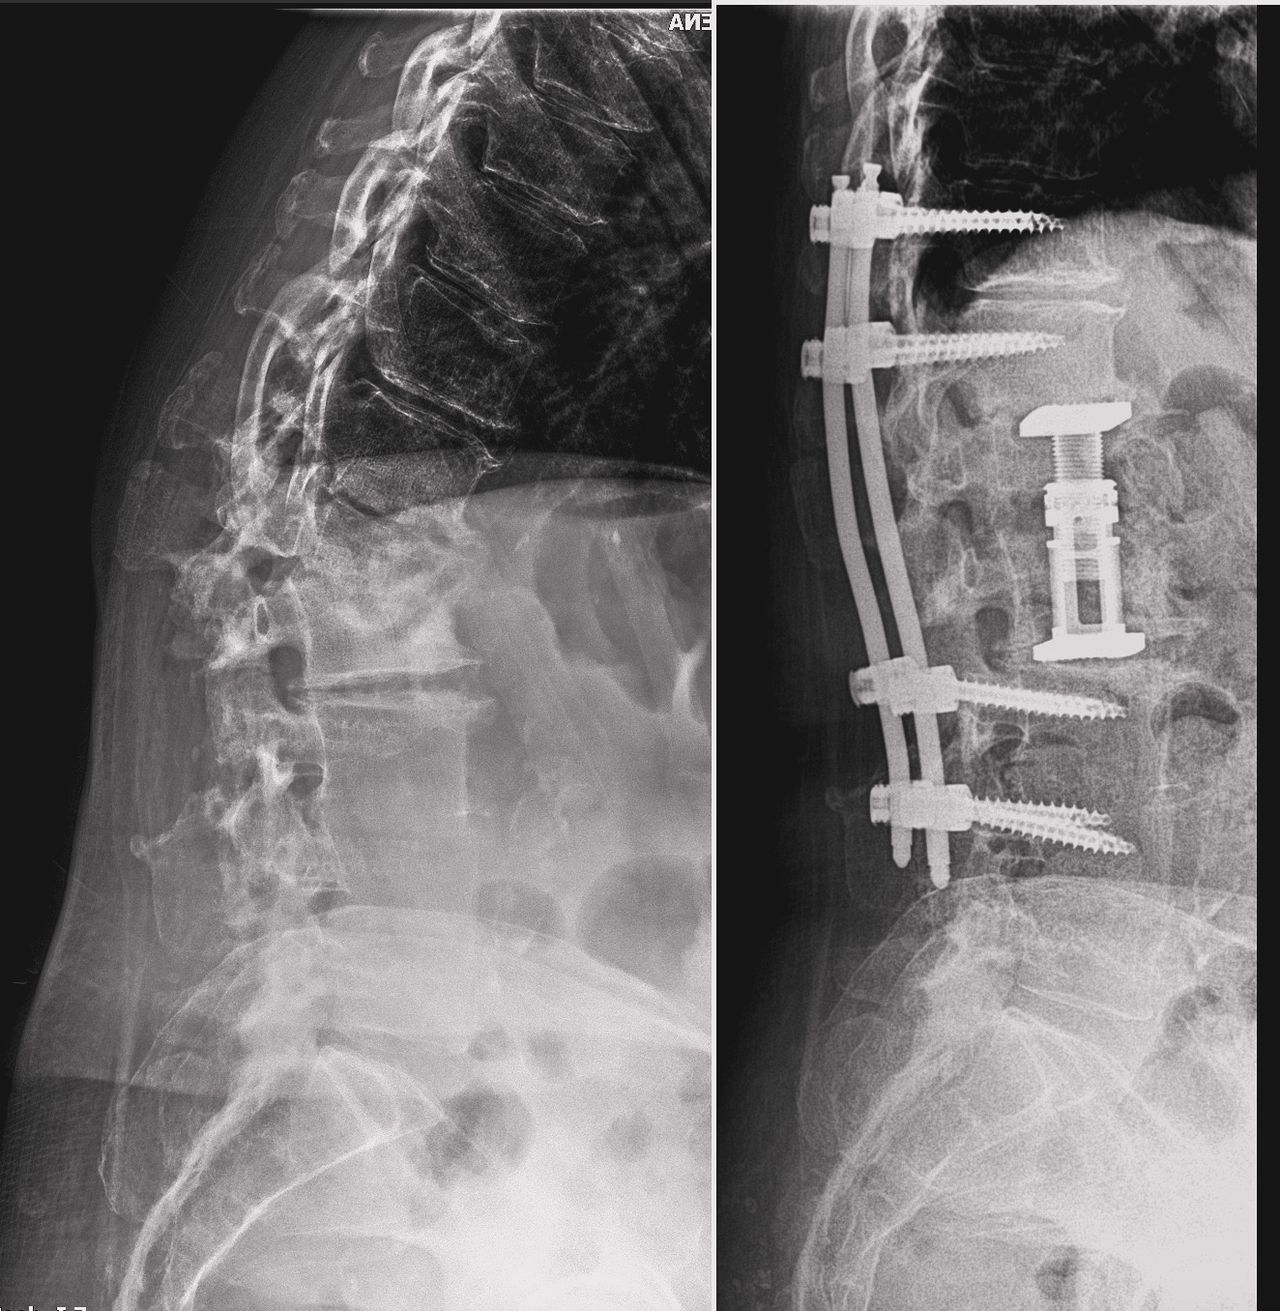

Foto e video